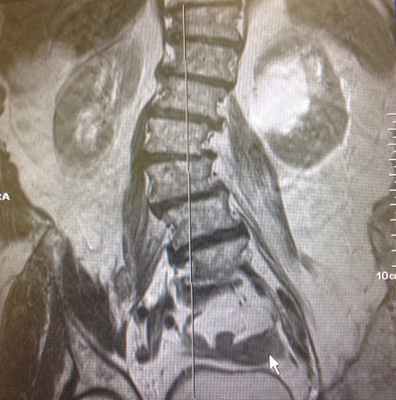

На мр-изображении видно, что большая поясничная мышца находится в состоянии отека, о чем свидетельствует изменение сигнальных характеристик. (гиперинтенсивная, яркая по t2)